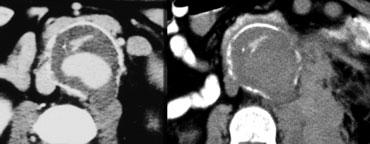

Gián đoạn khu trú của vôi hóa lớp nội mạc

Một dấu hiệu khác của vỡ phình sắp xảy ra hoặc rò rỉ khu trú là sự gián đoạn khu trú của vôi hóa lớp nội mạc.

Trong hầu hết các trường hợp này, chúng ta cũng có thể nhận thấy dấu hiệu canxi tiếp tuyến.

Trong những trường hợp này, hình ảnh cho thấy vôi hóa như đang chỉ ra ngoài chu vi dự kiến của túi phình.

Dấu hiệu canxi tiếp tuyến

Bên trái là một ví dụ khác về dấu hiệu canxi tiếp tuyến.

Vôi hóa lớp nội mạc hướng ra ngoài túi phình và có rò rỉ sau phúc mạc.